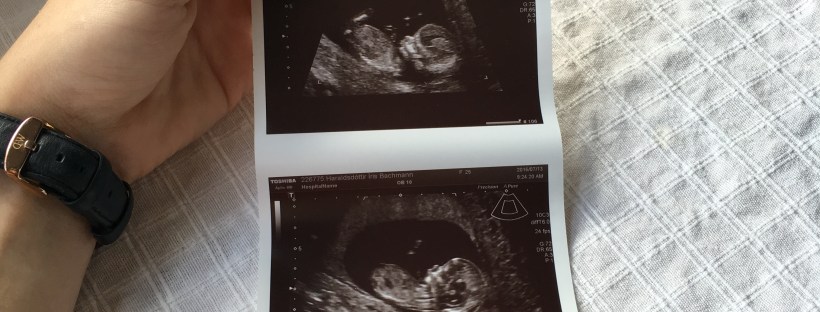

Ég átti sem sagt strákinn minn Þriðjudaginn 31. janúar 2017 kl 22:40

Hann var 3698g og 49 & 1/2 cm á lengd. Öllum heilsaðist rosalega vel eftir fæðingu, þrátt fyrir yfirlið og uppköst rétt eftir að prinsinn kom í heiminn.